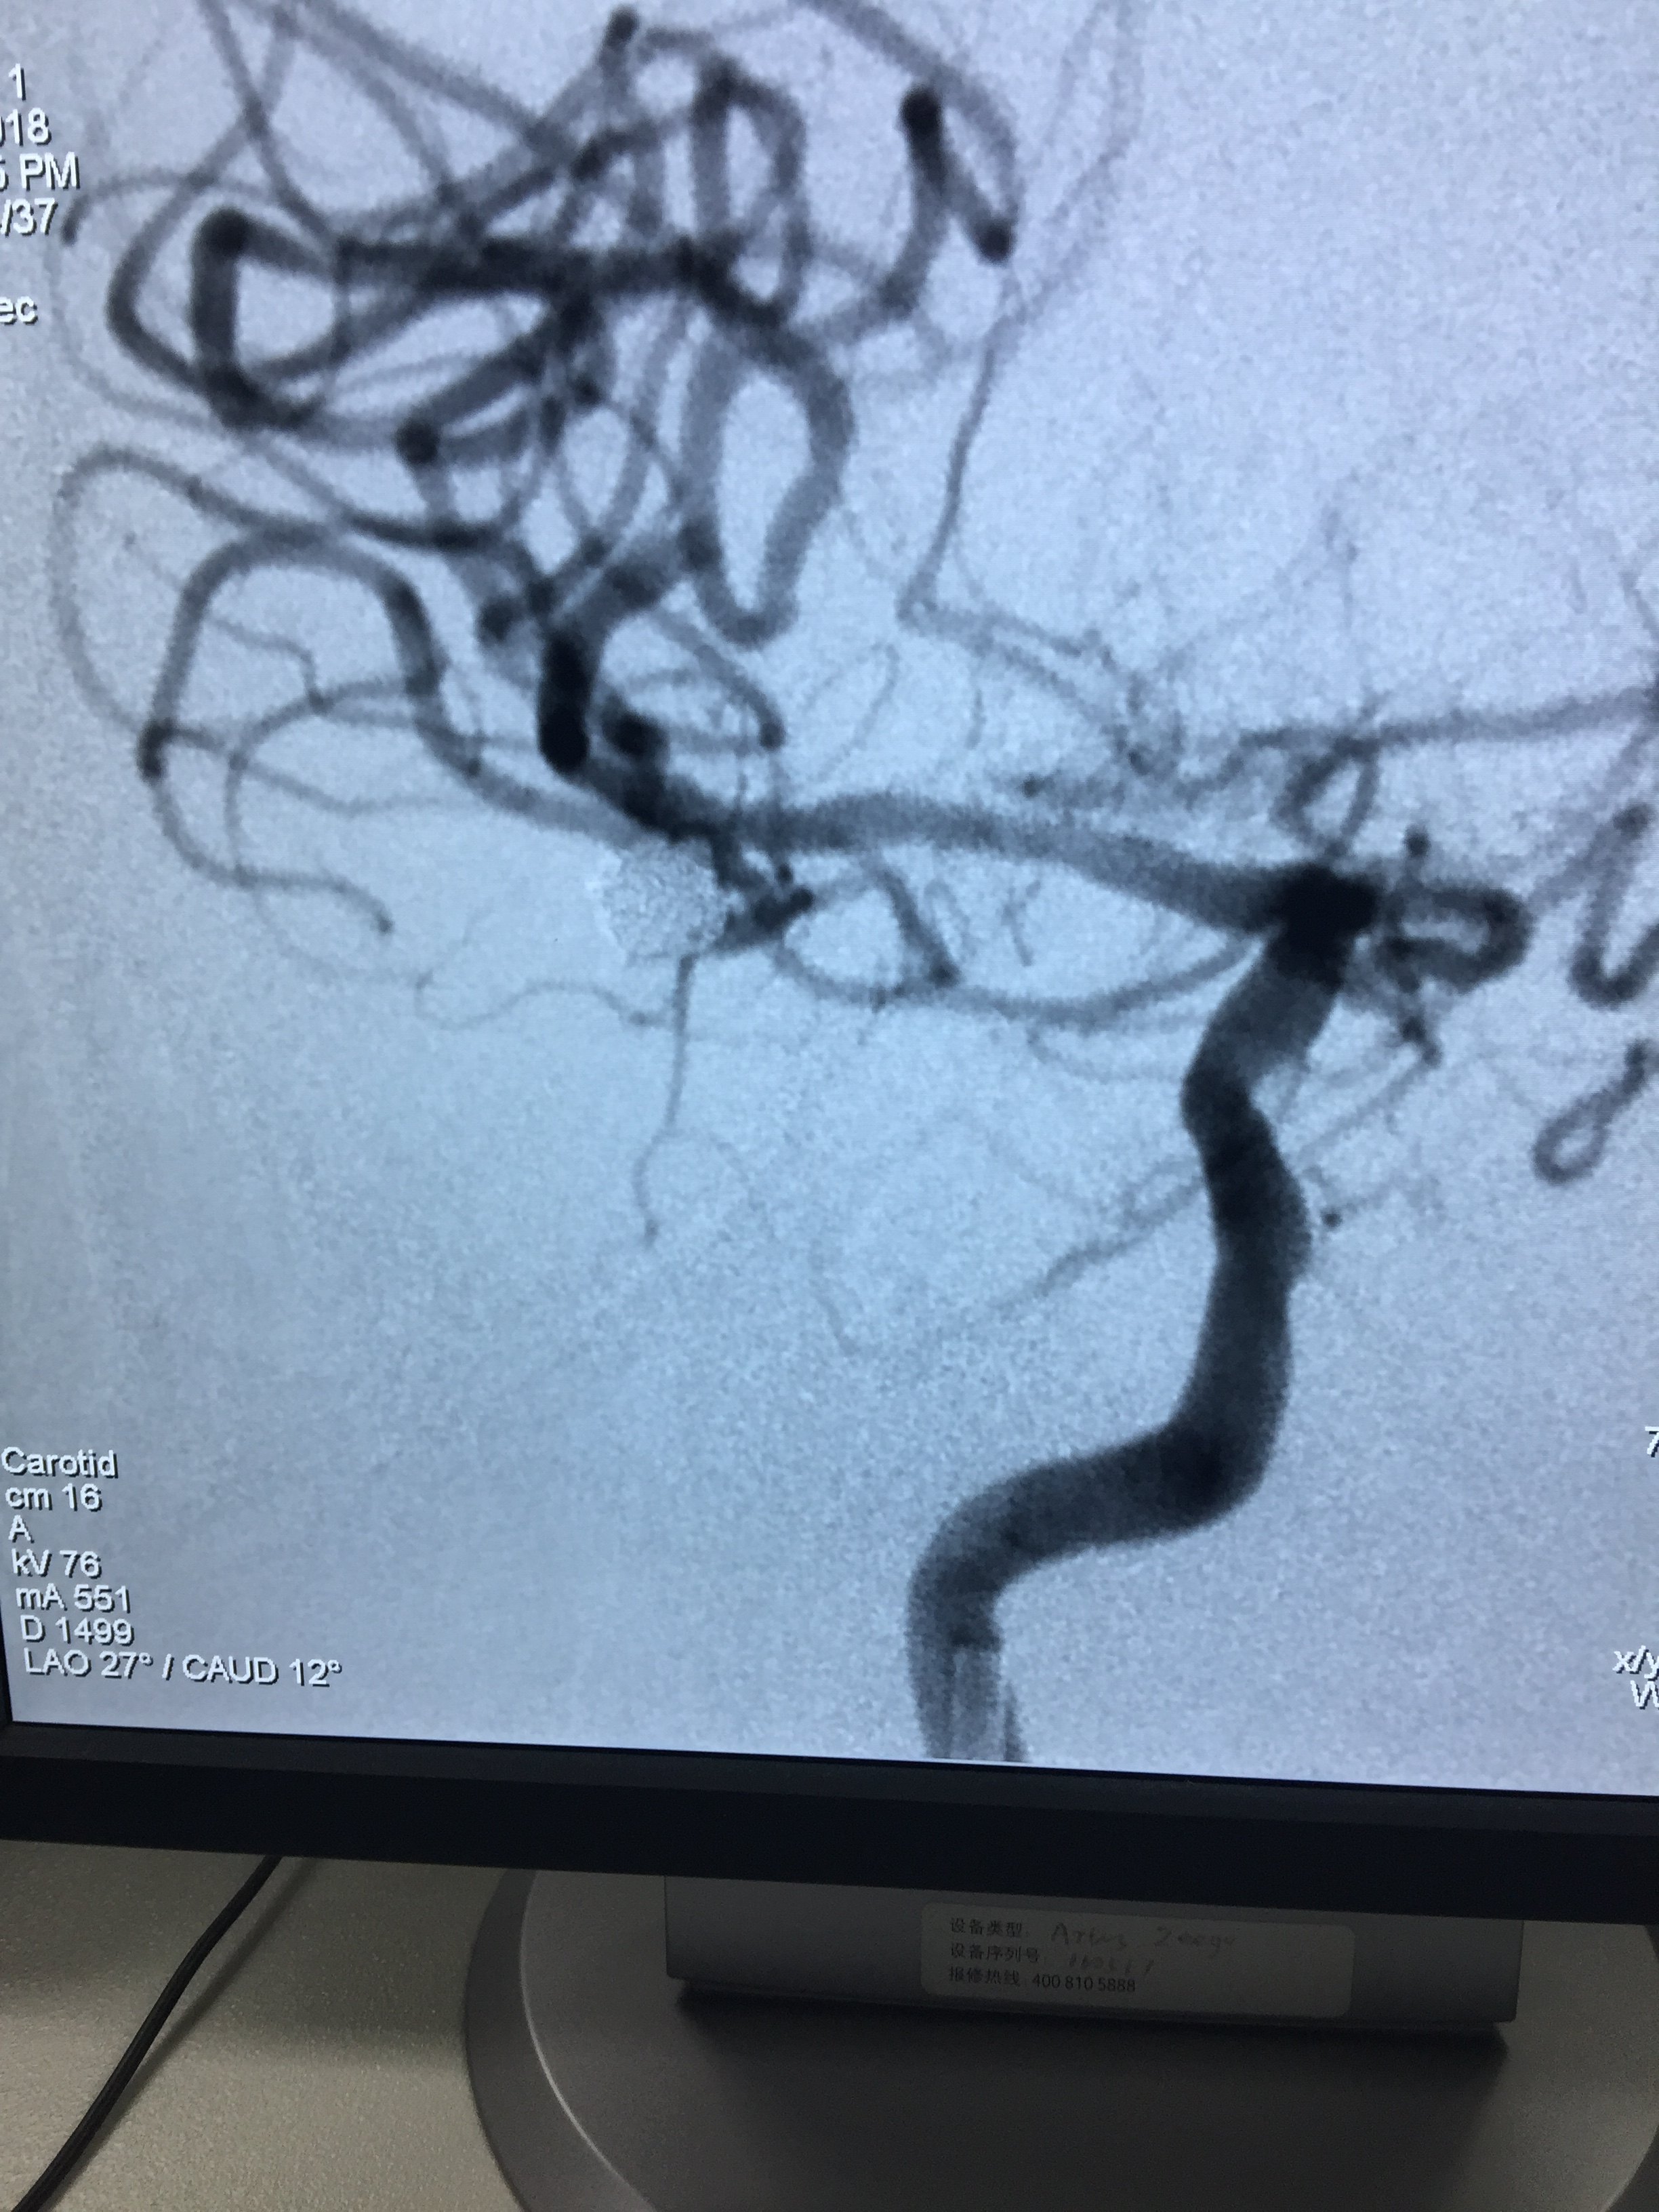

病例四:右侧大脑中分叉部动脉瘤

1534032349.png

该图片可能引起不适

1534032353.png